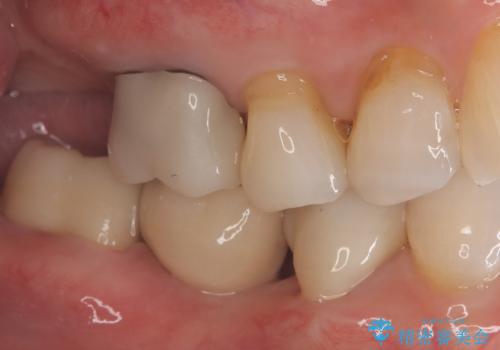

- 主訴:右下のセラミックのブリッジが何度も同じところで折れて壊れてしまう。

対合歯との咬合関係において、右下7番目と6番目の被せものの連結部がたわみやすい環境にあったため、ブリッジの新製ではなくインプラント治療を行いすべての歯を単冠仕上げとすることにしました。

何度も右下6、7間でブリッジが折れてしまうとのことでした。対合歯とブリッジの連結部が強く当たりたわみやすい状態でした。破折しずらい金属を使用したブリッジの選択もありましたが、支台歯(右下7)が失活歯場合、破折リスクが高く、破折してしまった場合にまたブリッジを外しての再治療になってしまう可能性を説明したところ、全て単冠仕上げとできるインプラント治療を希望されました。

右下5番のクラウンは、ブリッジを切断しそのまま使用していただいています。